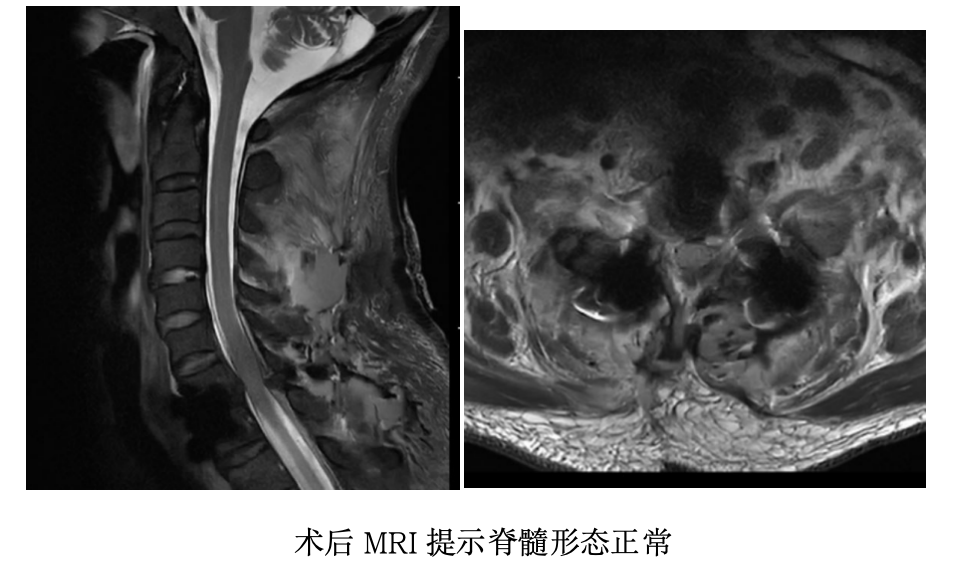

手术成功只是第一步。术后患者清醒后,四肢活动自如。复查影像显示:脱位已完全矫正,内固定位置完美,脊髓形态正常。

术后第3天,患者已能在支具保护下下床活动;术后1周,顺利出院。随访显示,患者疼痛基本消失,肢体功能正常,生活重回正轨。